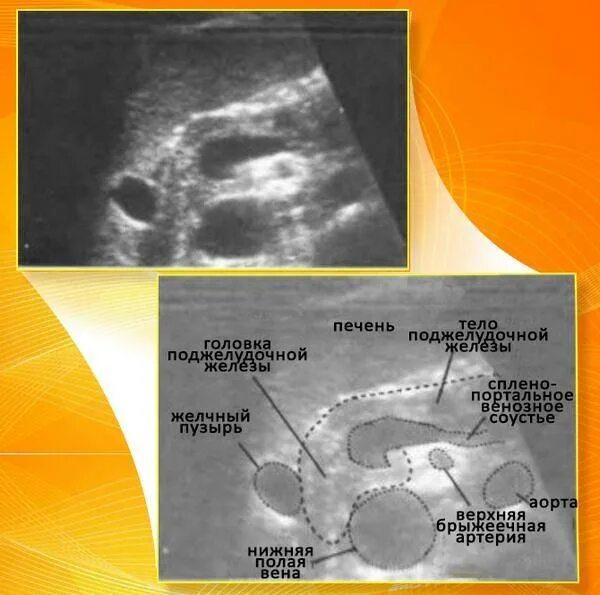

Повышенной эхогенности неоднородной структуры